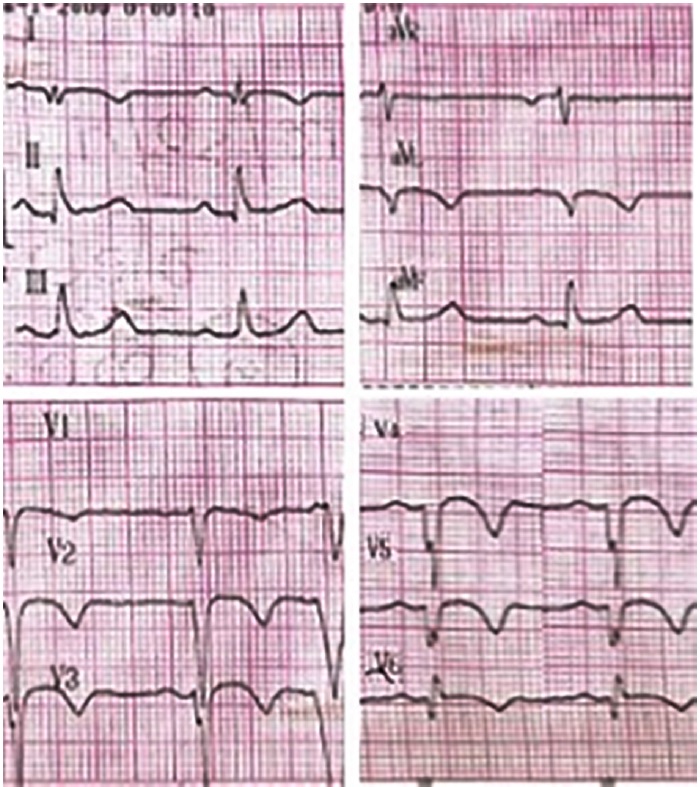

Presentamos un paciente de sexo masculino de 30 años, con antecedentes de miocardiopatía dilatada isquémico-necrótica no ateroesclerótica, con fracción de eyección ventricular izquierda (FEVI) reducida (35%) y aneurisma ventricular (Figura 1) por lesión iatrogénica, extrínseca, tras la sutura de la arteria descendente anterior, luego de una herida de arma de fuego y cirugía de urgencia. Evoluciona posteriormente con varias internaciones por episodios recurrentes de taquicardia ventricular monomorfa sostenida (TVMS) (Figura 2a) por lo que se decide colocación de un dispositivo cardiodefibrilador implantable (CDI) y ablación del sustrato, con evolución favorable.

Fig. 2b Electrocardiograma posterior a la cardioversión eléctrica donde se observa ritmo sinusal a 65 lpm, con presencia de ondas Q y T negativas en cara anterolateral, compatible con secuela de necrosis y trastornos en la repolarización